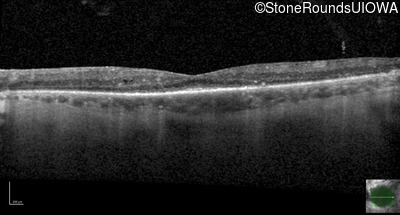

Optical Coherence Tomography - Left - 20/40 +1

Exemplar / OCT Stack

OCT Stack